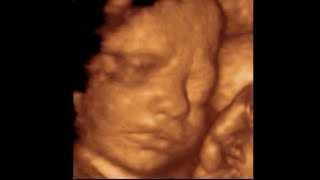

Ultrasound Scans Is There A Difference Between 3d And 4d Scans

Hire a 3D scanner. Reasons for choosing to go for a private scan included wanting a 3D scan a 4D scan or being scanned because they were having IVF. If you find yourself in the position of having to shop around for 3D scanning services we understand that it can be a daunting task.

2d And 3d Versus 4d Pregnancy Scans Youtube

3d 4d Baby Scan Ultrasound Scans Ultrascan Ie

3d 4d Ultrasound Baby Scan Window To The Womb Ltd Baby Scan Baby Ultrasound 4d Ultrasound

4d Pregnancy Bonding Ultrasound The Ultrasound Clinic

When Is The Best Time To Get A 3d Ultrasound Mother Nurture Ultrasound

3d Ultrasound And 4d Ultrasound During Pregnancy Babycenter